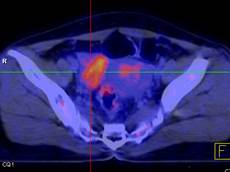

Hình 1. Bệnh nhân Nguyễn Th. H., nữ, 43 tuổi, chẩn đoán ung thư buồng trứng phải. Trên hình FDG-PET/CT thấy khối u buồng trứng phải tăng hấp thu FDG.